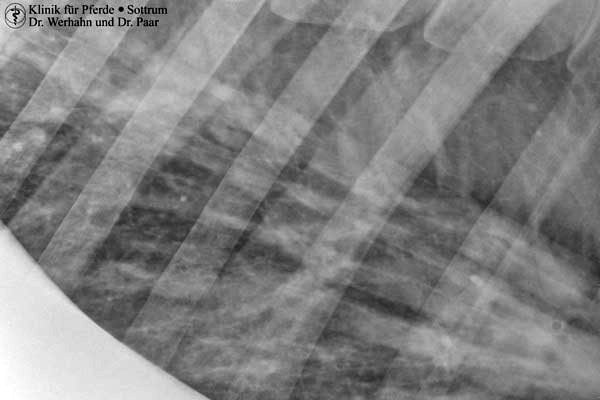

Neben den Standardaufnahmen im unteren Gliedmaßenabschnitt ist somit auch die röntgenologische Untersuchung von Ellbogengelenk, Schulter, Knie und Hüftgelenk, Halswirbelsäule, Rücken sowie von Kopf und Zähnen in sehr guter Qualität und unter Berücksichtigung der Anforderungen des Strahlenschutzes für die exponierten Personen möglich.

In Verbindung mit einem zusätzlichen mobilen Hochfrequenz-Röntgengenerator steht das direkte digitale Röntgen auch dem Chirurgen intraoperativ zur Verfügung.